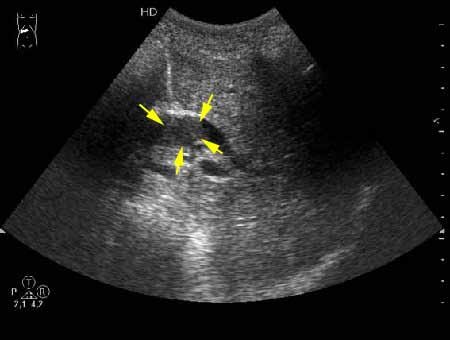

К сожаления, практически не видно. Если Вас не затруднит, пометьте стрелкой зону интереса.

А.М.Шифрин писал(а):К сожаления, практически не видно. Если Вас не затруднит, пометьте стрелкой зону интереса.

Дело в том, что в холедохе имеется нечто изоэхогенное (не знаю, видно ли это нечто на ваших мониторах). Врач УЗИ при осмотре перед поступлением в стационар на основании этой картины в заключении отметил возможность опухоли холедоха.

Гнойный холангит на фоне обструкции БДС конкрементом (камень вне скана). В холедохе определяется желчь с осадком, которая может быть ошибочно принята за его опухоль.